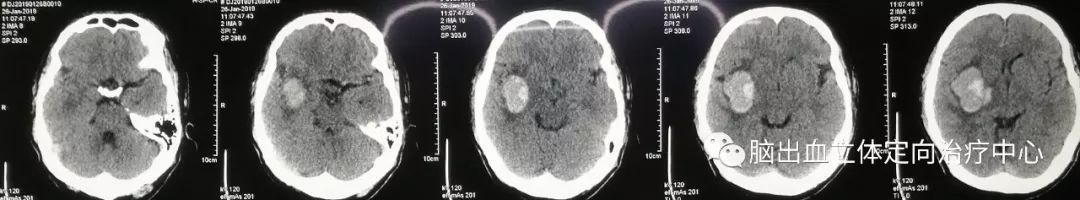

入院时CT:

复查CT示:侧脑室、三脑室较前受压明显,血肿周围分层低密度明显

仔细观察CT片可见血肿呈分层现象